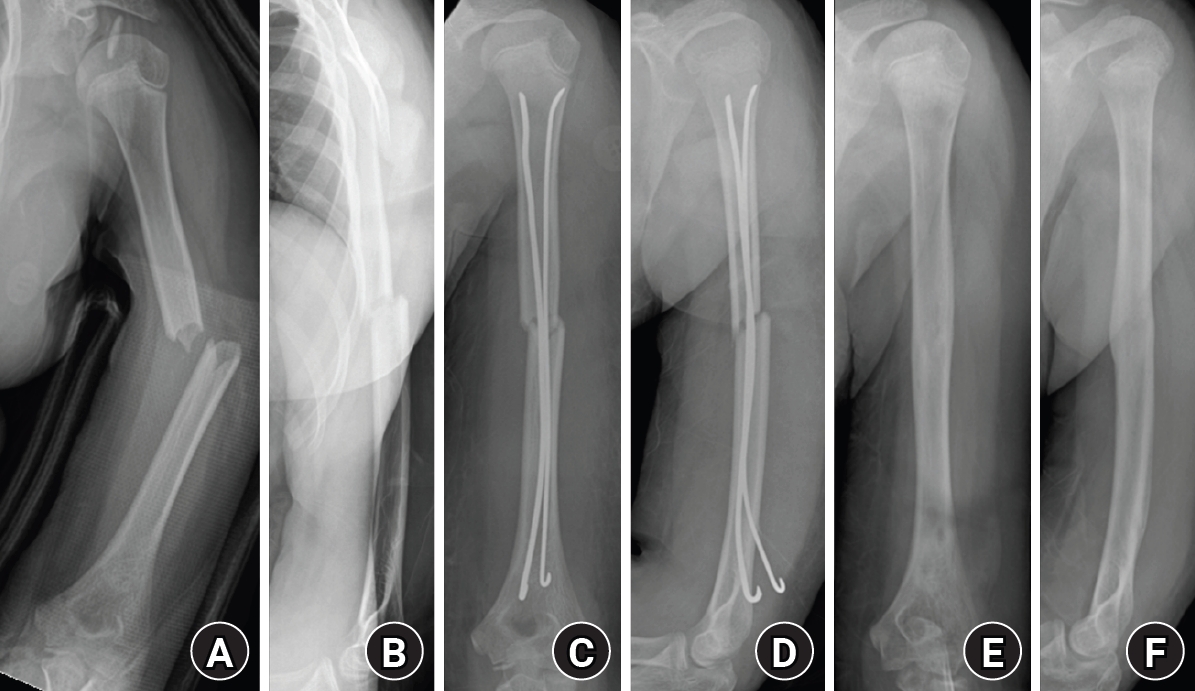

A single or double pre-bent titanium elastic nail (diameter, 2.0–3.0 mm) was chosen, with a diameter approximately one-third of the narrowest portion of the medullary canal [8]. In smaller humeri, the available canal diameter and posterior entry approach sometimes limited the maximal nail size, so a single nail was used to avoid excessive force during insertion. When the canal width allowed, two nails were inserted to achieve optimal end-point divergence and three-point elastic fixation. Proper alignment and rotational stability were confirmed under fluoroscopic control. After satisfactory reduction and fixation were achieved, the nail was cut and impacted beneath the posterior cortex to prevent soft-tissue irritation. Postoperatively, the arm was supported in a simple sling for comfort. Early gentle shoulder and elbow motion was initiated within the first postoperative week, and full range of motion (ROM) was allowed once radiographic callus formation was evident. All implants were removed after radiologic union was achieved (Fig. 2).

Fig. 2.

Radiographs of a representative case demonstrating successful bone healing following elastic stable intramedullary nailing fixation. (A, B) Preoperative anteroposterior and lateral radiographs showing a midshaft humeral fracture. (C, D) Immediate postoperative radiographs demonstrating satisfactory fracture alignment and stable fixation with elastic nails. (E, F) Follow-up radiographs obtained after implant removal showing complete bone union and restoration of normal humeral alignment.

Fig. 2. Radiographs of a representative case demonstrating successful bone healing following elastic stable intramedullary nailing fixation. (A, B) Preoperative anteroposterior and lateral radiographs showing a midshaft humeral fracture. (C, D) Immediate postoperative radiographs demonstrating satisfactory fracture alignment and stable fixation with elastic nails. (E, F) Follow-up radiographs obtained after implant removal showing complete bone union and restoration of normal humeral alignment.